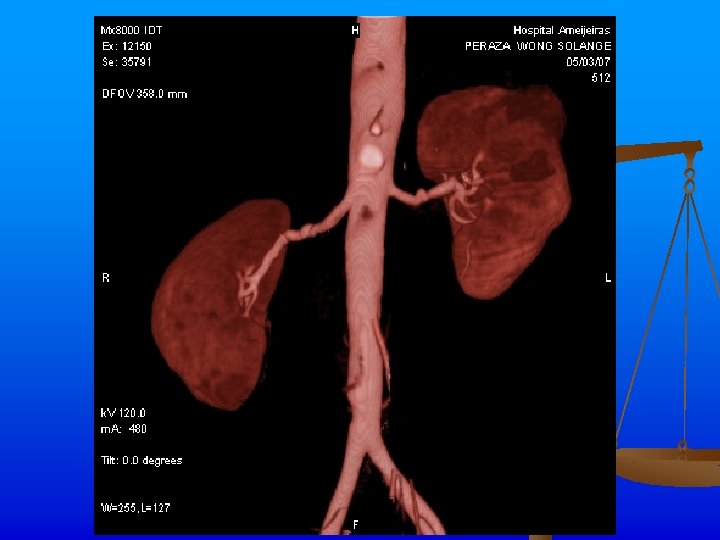

Exámenes Complementarios n n n Rx de tórax: Ligeros signos de hiperinsuflaciòn pulmonar. ICT normal. Índice de presiones de MI dentro de límites normales. Angio TAC: Se realiza angio. TAC abdominal inyectándose 120 ml de contraste, apreciándose áreas de estenosis y dilatación de ambas arterias renales, con un patrón arrosariado y zonas de hipoperfusión corticales en los polos de ambos riñones. Hay buena eliminación y concentración renal bilateral.